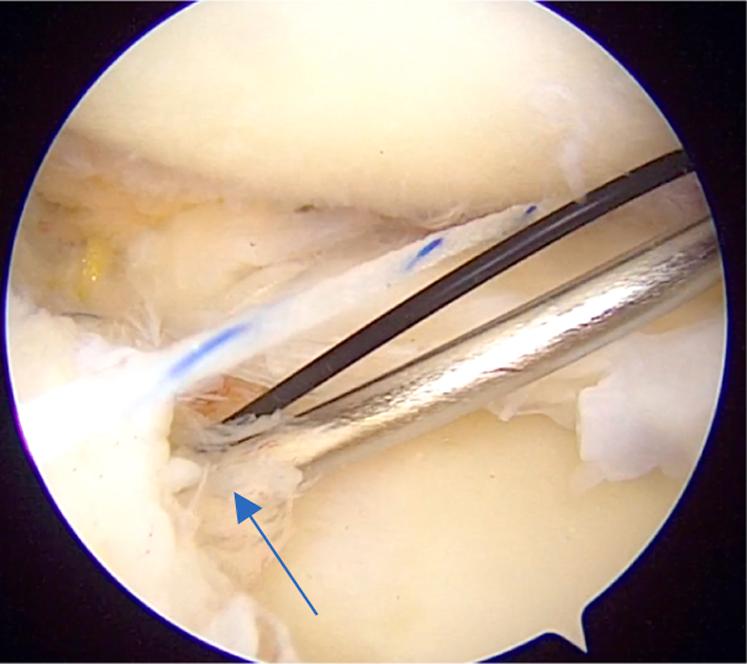

The meniscus plays a very important role in normal functioning of the knee joint. It acts as a shock absorber, gives stability to the knee joint, delays the onset of osteoarthritis, provides load sharing, and so on. It is a well-known fact that after meniscectomy, there is a significant increase in joint reaction forces leading to early osteoarthritis. Hence, in the past decade, meniscal repair has gain enormous importance and various techniques have been developed to repair the meniscus. Conventionally, posterior-third meniscal tears are repaired with all-inside and outside-in techniques whereas middle-third meniscal tears are repaired with all 3 methods: inside out, outside in, and all inside. For tears of the anterior horn of the meniscus, only the outside-in method is used. We have developed a method for repair of chronic unreduced, retracted bucket-handle anterior horn lateral meniscal tears, in which we combined the use of both the outside-in and all-inside methods of repair. Hence, this method is called modified outside-in meniscal repair for chronic retracted bucket-handle anterior horn lateral meniscal tears.

半月板在膝关节的正常功能中起着非常重要的作用。它充当减震器,为膝关节提供稳定性,延缓骨关节炎的发生,分担负荷等等。众所周知,半月板切除术后,关节反应力会显著增加,导致早期骨关节炎。因此,在过去十年中,半月板修复变得极其重要,并且已经开发出各种技术来修复半月板。传统上,后三分之一半月板撕裂采用全关节内和由外向内技术修复,而中三分之一半月板撕裂则采用三种方法修复:由内向外、由外向内和全关节内。对于半月板前角的撕裂,仅使用由外向内方法。我们已经开发出一种修复慢性未复位、回缩的桶柄状前角外侧半月板撕裂的方法,在该方法中,我们结合使用了由外向内和全关节内两种修复方法。因此,这种方法被称为用于慢性回缩桶柄状前角外侧半月板撕裂的改良由外向内半月板修复术。